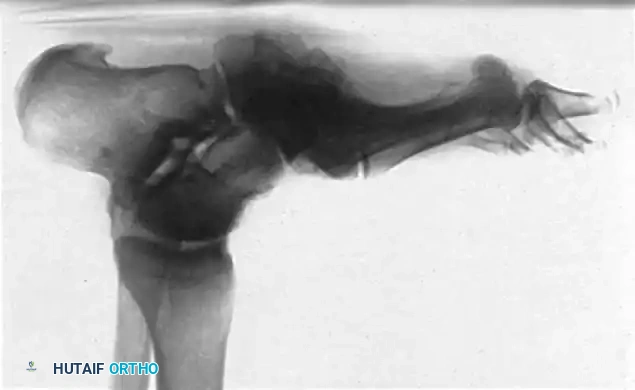

In the presence of motor neuropathy, the intrinsic musculature of the foot atrophies, leading to an intrinsic-minus foot posture. This results in the classic claw toe deformity: hyperextension at the metatarsophalangeal (MTP) joints and flexion at the proximal interphalangeal (PIP) joints. Consequently, the plantar fat pad is drawn distally, leaving the metatarsal heads prominent and unprotected against vertical and shear forces during the terminal stance phase of gait.

• Claw Toe Correction: Correction at the MTP and PIP joints is often necessary. This may involve extensor tendon lengthening, dorsal MTP capsulotomy, and PIP arthroplasty or arthrodesis.

• Hallux Interphalangeal Arthrodesis: Fixed flexion deformities of the hallux interphalangeal joint create massive pressure at the distal tip of the toe. Arthrodesis of this joint, often combined with extensor hallucis longus (EHL) lengthening, is highly effective.